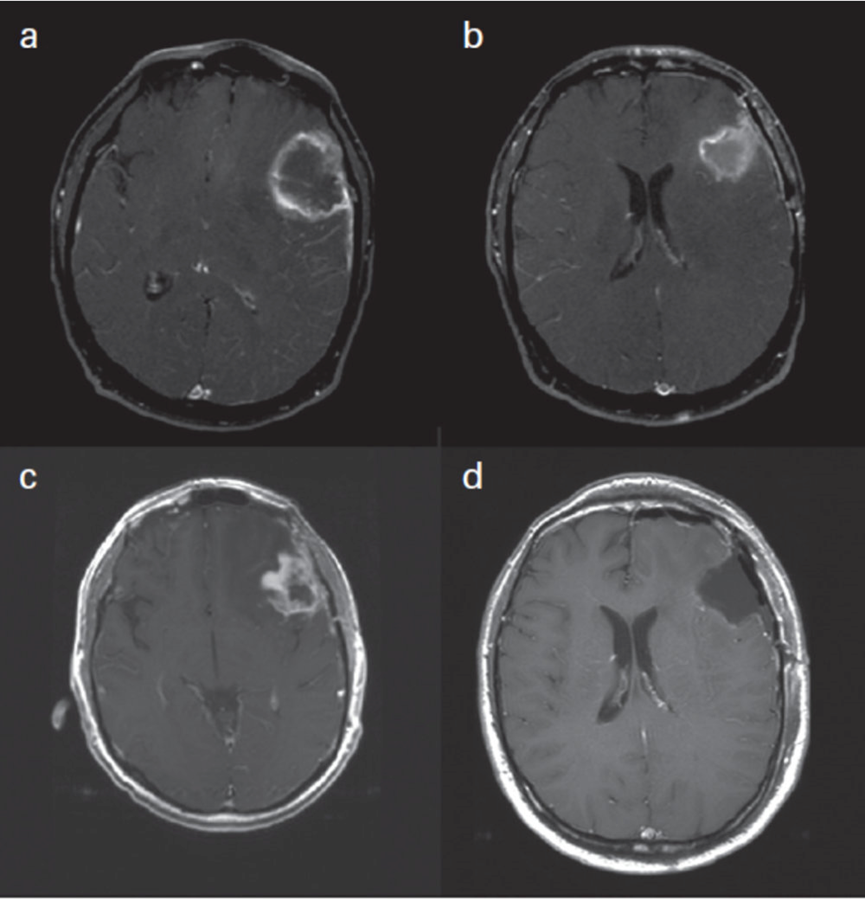

圖A顯示了一個邊界不清的強化病灶,中心壞死或不強化。圖B顯示了切除術(shù)后MRI,可見切除腔。圖C的隨訪MRI顯示,切除腔周圍出現(xiàn)厚而邊界不規(guī)則的強化,提示可能存在疾病進展。圖D的再次手術(shù)切除標(biāo)本病理學(xué)檢查顯示,未見活性的腫瘤組織,僅有大量壞死組織。因此,該病例為手術(shù)證實的假性進展的典型例證。

更新的高等級膠質(zhì)瘤反應(yīng)評估標(biāo)準:神經(jīng)腫瘤學(xué)工作組的反應(yīng)評估。J Clin Oncol. 2010年4月10日;28(11):1963-72,第1965頁。